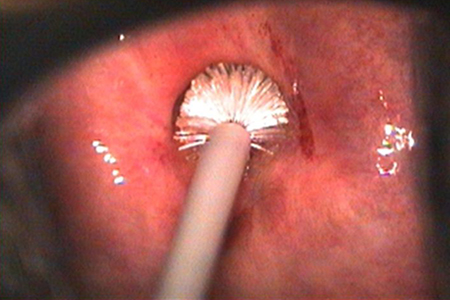

Introdução do espéculo

- Este deverá ser introduzido em sentido longitudinal-oblíquo, com um ângulo aproximado de 45º, no sentido horário (para desviar da uretra), imprimindo delicadamente um trajeto direcionado posteriormente, ao mesmo tempo em que se gira o instrumento em sentido horário, para o eixo transversal.

Coleta da ectocérvix

O material é coletado com um movimento giratório de 360 graus em torno do orifício cervical, para que toda superfície do colo seja raspada e representada na lâmina.

Coleta da Endocérvice:

Esta coleta é realizada com a escova Campos da Paz, também chamada de escova endocervical.

A escova deve ser inserida no orifício externo do colo e girada em um movimento de 90º-180º em sentido horário.

É aconselhável que se realize este movimento rápido para evitar que haja lesão do canal e sangramento, diminuindo a qualidade da amostra